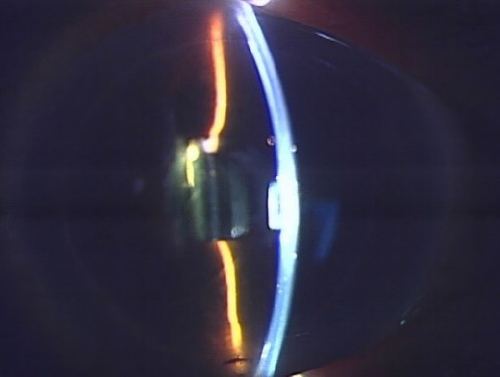

手術

2.4mm~3mm程度の切開創から濁った水晶体を「超音波乳化吸引術」で砕いて吸引し、代わりに透明な人工レンズ「眼内レンズ挿入術」を行います。